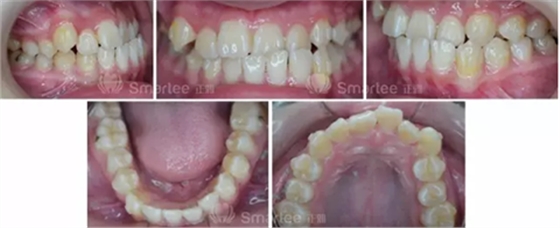

主訴:面部左右不對稱,左側(cè)前牙反牙合。

(口內(nèi)照片)

1)安氏Ⅲ類錯牙合

2)左側(cè)前牙反牙合

3)前牙區(qū)擁擠,個別牙扭轉(zhuǎn)

4)上頜中線右偏